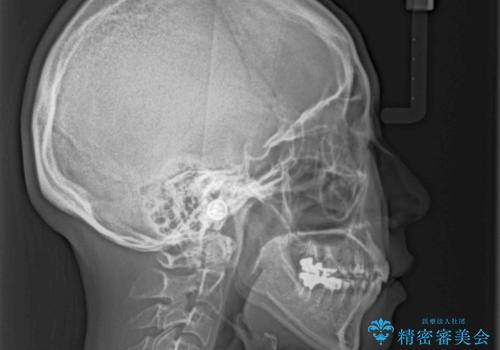

総合歯科治療 矯正治療と失活歯のセラミック補綴治療

- 失活により変色した歯と不揃いな口元を気にして来院された患者様です。

口元をインビザラインにより歯列を整え、その後に失活している奥歯をオールセラミッククラウンにて補綴治療することとしました。